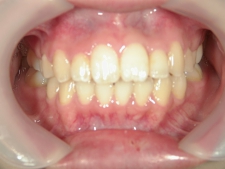

矯正歯科 治療後矯正歯科 プチワイヤー矯正 治療後矯正歯科(プチワイヤー矯正)治療後

矯正歯科 治療後

no.8_8495_治療後_左.jpgno.8_8495_治療後_正面.jpgno.8_8495_治療後_右.jpg